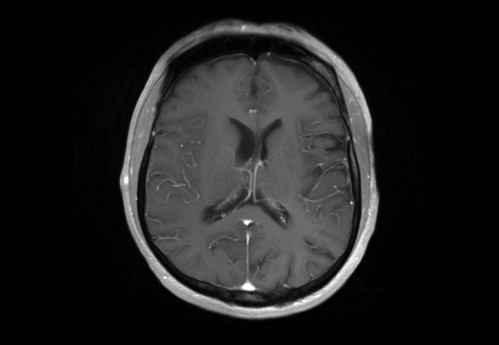

Sie behandeln einen 48-jähriger Mann, von Beruf Architekt. In der Anamnese erfahren Sie, dass er leidenschaftlich Gitarre spiele und er berichtet, dass ihm seit zwei Wochen in der rechten Hand die nötige Koordination fehle. Auch das Plektrum würde ihm immer wieder aus den Fingern gleitet.

Eine Magnet-Resonanz-Tomografie (MRT) des Kopfes wurde durch den ambulant behandelnden Neurologen bereits veranlasst.